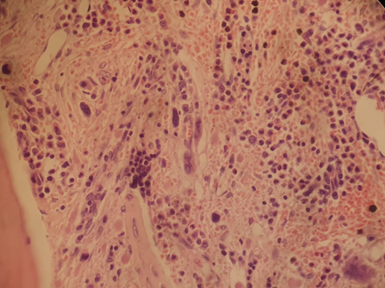

Figura 1. Anatomía patológica de MO con hallazgos compatibles con síndrome mieloproliferativo crónico con aumento de trama de reticulina (MF1).

Paciente varón de 58 años de edad con antecedentes de hipertensión arterial, diabetes mellitus tipo 2 y colitis ulcerosa (CU), sin seguimiento adecuado de dichas patologías. Consulta en el año 2007, a sus 43 años de edad, por dolor abdominal. Se constata en laboratorio poliglobulia (Hto 67%, Hb 20 gr/dl), trombocitosis (plaquetas 1.273.000/mm3) y leucocitosis con neutrofilia (GB 14.000/mm3 con 78% neutrófilos segmentados). Al examen físico presenta esplenomegalia. No accede a realizarse estudio de medula ósea, por lo que se solicita mutación JAK2 V617F, siendo detectable. Se diagnostica policitemia vera (PV) de alto riesgo, iniciando tratamiento con hidroxiurea (HU), con mala adherencia (toma esporádica ante dolor abdominal). En 2015 consulta por primera vez a nuestra institución por exacerbación de dolor abdominal, que no cede con HU, asociado a pérdida de peso. Al examen físico presenta abdomen distendido con esplenomegalia a 8 cm por debajo del reborde costal (bazo de 200 mm por ecografía). Se realiza re evaluación de enfermedad presentando en estudios realizados: Hb 12,5 gr/dl, Hto 37%, GB 56.700/mm3 (segmentados 46%, basófilos 3%, eosinófilos 2%, linfocitos 6%, promielocitos 12%, mielocitos 9%, metamielocitos 9% y blastos 3%), plaquetas 939.000/mm3, estudio citogenético de médula ósea (MO) 46,XY, der(22)t(9;22)(q34;q11)[20], biopsia de MO con celularidad del 80%, con relación mielo-eritroide 4/1, trama de reticulina aumentada y mielofibrosis grado 1 (MF1) (Figura 1). Estudio molecular qPCR BCR-ABL1 p210 indetectable. No se realiza transcriptos atípicos (p190 - p230). Con los hallazgos antes mencionados se plantea el diagnóstico de leucemia mieloide crónica (LMC) Ph+, JAK2+ en fase crónica con Sokal de alto riesgo y Hasford de riesgo intermedio.